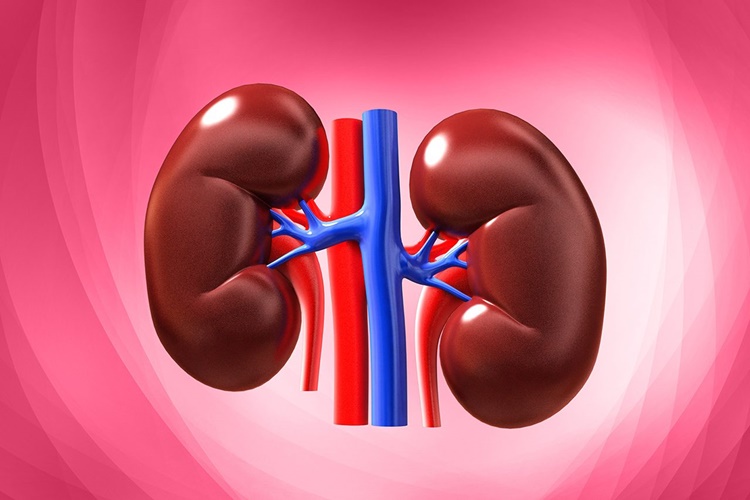

Böbrekler Nerede Bulunur?

Böbrek organları, karnınızın arkasında, göğüs kafenizin

hemen altında, omurganızın her iki tarafında, sırta yakın bir şekilde yer

almaktadır. Böbrekler, kahverengi fasulye şeklinde iki küçük organa verilen ad

olarak bilinmektedir. Bireyin bel hizasında, omuriliğin her iki yanında göğüs

kafesinin altında, sırta daha yakın bir konumda vücudun iki yanında birer tane

yer almaktadır.